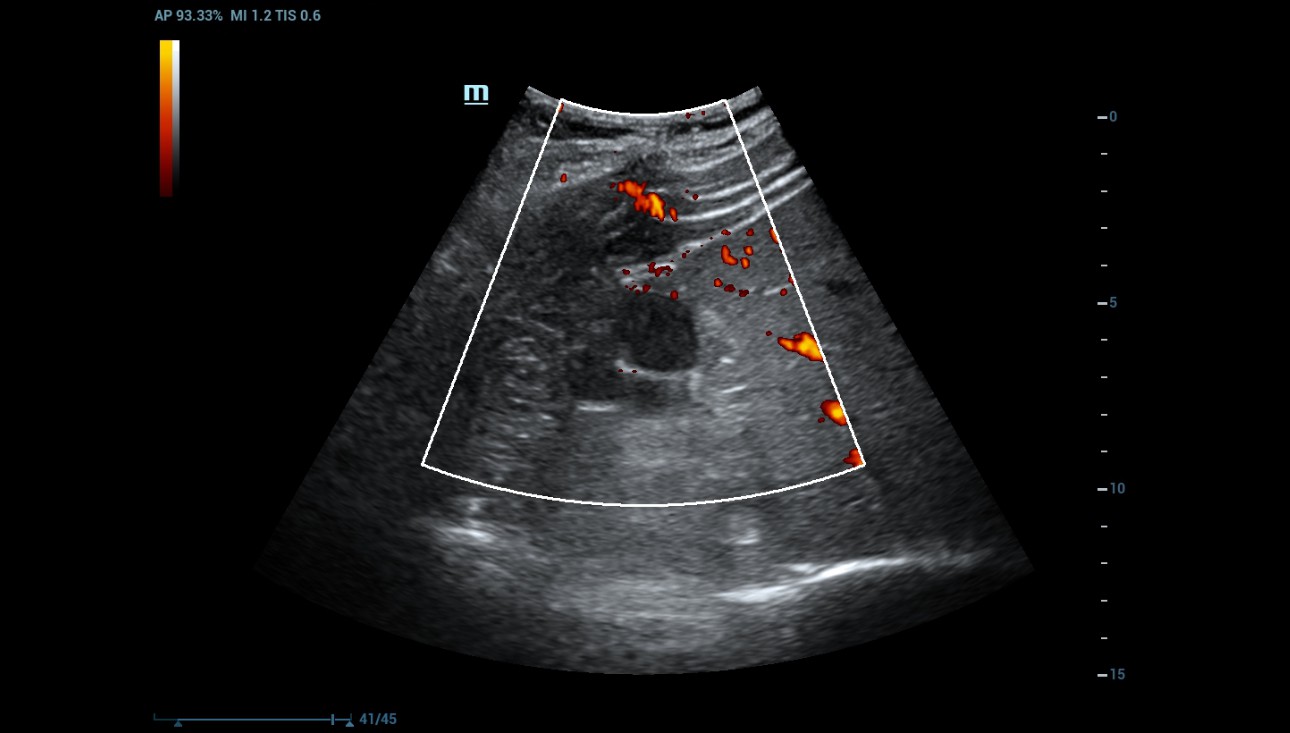

Power Doppler was used to evaluate for internal flow within the complex cystic mass with indeterminate results. (Figure 3).